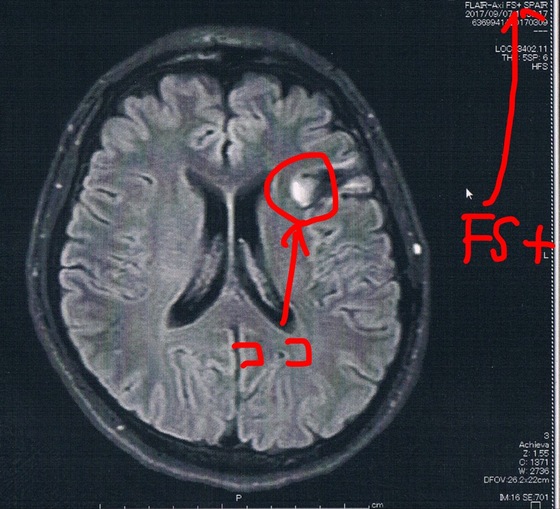

今回2017/9/7(手術後39か月)のMRI画像